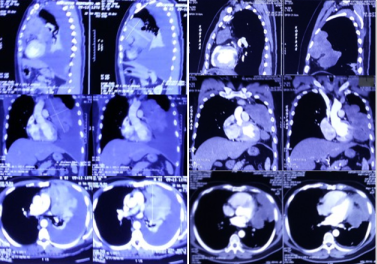

Celebrating a Decade of Survival Following “Untreatable” Lung Cancer

In 2013, after exhausting all conventional options including surgery and intensive chemotherapy, a patient diagnosed with aggressive lung cancer was left with little hope. Faced with a dire prognosis, they turned to ECCT (Electro-Capacitive Cancer Therapy) as a pioneering alternative. Against the odds, the therapy facilitated a remarkable recovery, leading to a cancer-free life that has now spanned over 12 years. This journey serves as a powerful testament to the potential of non-traditional treatments in providing a second chance to those facing the most difficult-to-reach and advanced-stage cancers.